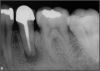

The rules for placement of a post depend on good retention: the greater the length, the greater the retention.3 Also, two-thirds of the length of the root is ideal, but 4 to 5 mm of apical gutta-percha is essential because anything less than that will disrupt the seal.8 Figure 14 shows a case where a patient had a post, core, and crown. The threaded post was shorter than ideal because the tooth was longer. Not visible was the mental foramen underneath. The patient did not have the financial resources to have the case redone. However, when the post would be removed, the clinician would need to trephine or use an ultrasonic around it, making the access bigger than an ideal conservative access. Potentially, the crown would come off. The patient did not have finances for re-treating the tooth and could not have an apicoectomy because the mental foramen was directly under the tooth.

Fig 14. The post was shorter than ideal.

Figure 14